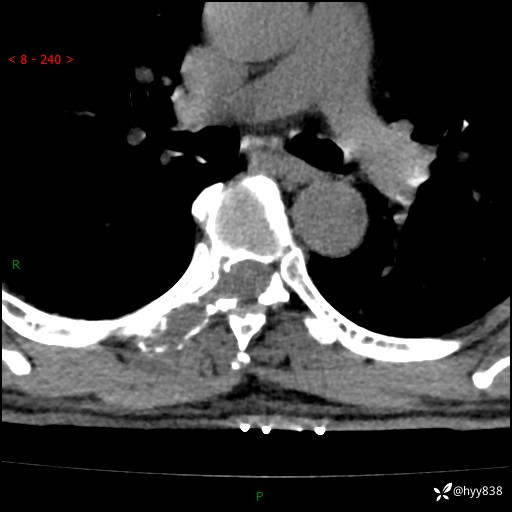

辅助检查:CT MRI

axi T2WI